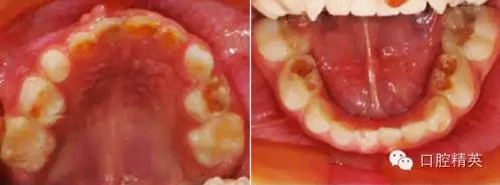

臨床檢查:頜面部及頸部未見明顯異常??谇恍l(wèi)生狀況尚可, 52,61,62,63,73唇舌面齲,54,64,74,84牙合面齲壞,腐質(zhì)中等,叩(-),松(-),牙齦未見明顯異常;75牙合面深齲壞,大量軟腐,叩(-),松(-),牙齦未見明顯異常,腐質(zhì)未去凈見露髓孔;51大面積齲壞,大量腐質(zhì),叩(+),松(Ⅰ),唇側(cè)牙齦可見5mm×6mm的包,軟;余牙未見異常。

診斷:S-ECC

①52,61,62,63,73,54,64,74,84去腐備洞,氫氧化鈣墊底,全酸蝕,DE-BOND加3M樹脂充填,調(diào)合,磨光。

②75,51局麻下開髓、拔髓,根管預(yù)備,生理鹽水沖洗,Vitapex根充,鋅汀墊底,全酸蝕,DE-BOND加3M樹脂充填,調(diào)合,磨光。